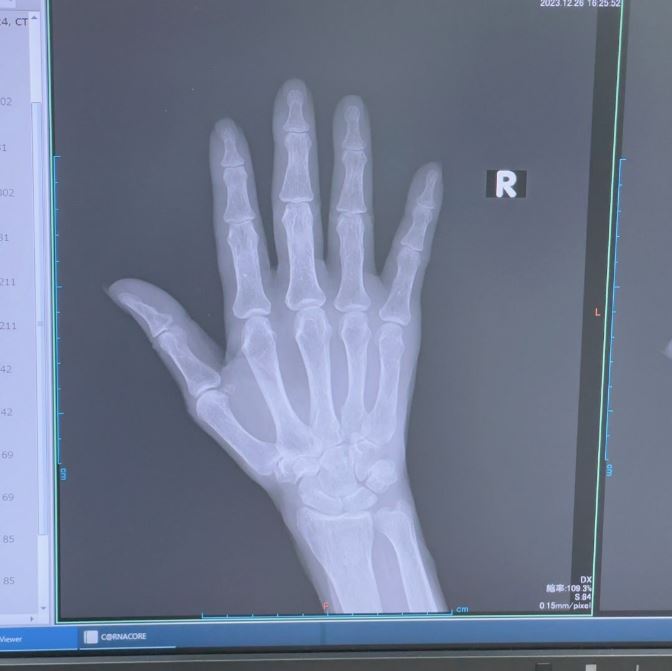

ブログには、整形外科を受診したときのことが記されていて、「昨日受診した○○整形外科の院長先生の治療には感動しました‼️」と書き出し「小指 第3関節の下 綺麗に折れてるのが 分かりますよね」「折れた骨が 内側に入り込んでるのが分かります」と骨折した指のレントゲン写真とともに説明。